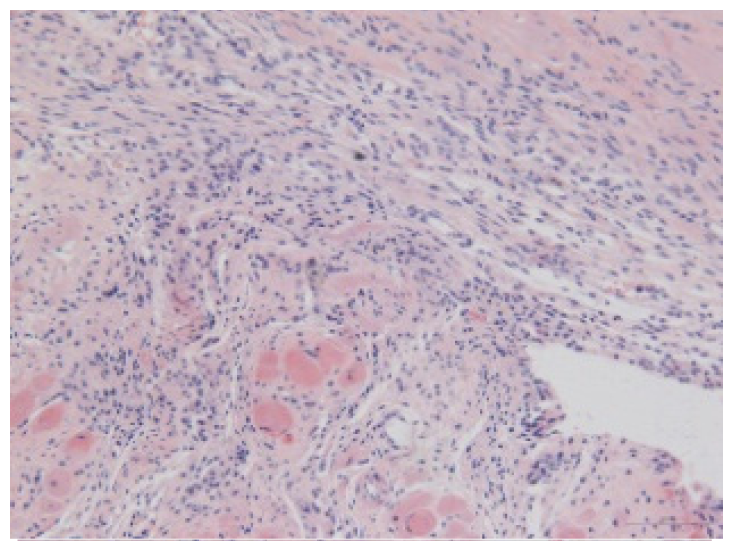

2.1.6. CoPP Treatment Diminished Infarct and Peri-Infarct Area in ISHR Model

2.1.7. CoPP Treatment Inhibited Ventricular Remodeling of Post-Infarction in SHR

| Groups | Masson (macroscopic) | Masson (×200) | Infarct area (HE ×200) | Peri-infarct area (HE ×200) |

|---|---|---|---|---|

| WN | ![]() | ![]() | ![]() | |

| SMN | ![]() | ![]() | ![]() | ![]() |

| SMC | ![]() | ![]() | ![]() | ![]() |

| SMS | ![]() | ![]() | ![]() | ![]() |